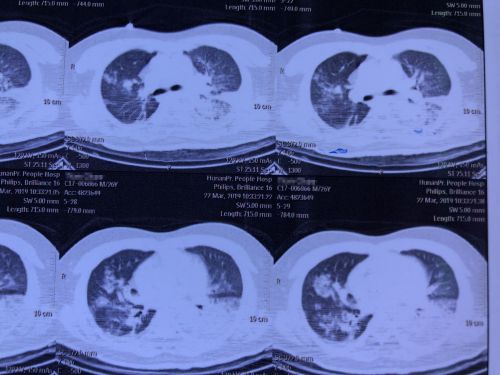

肺部ct显示:双肺多发大片斑片及实变影。